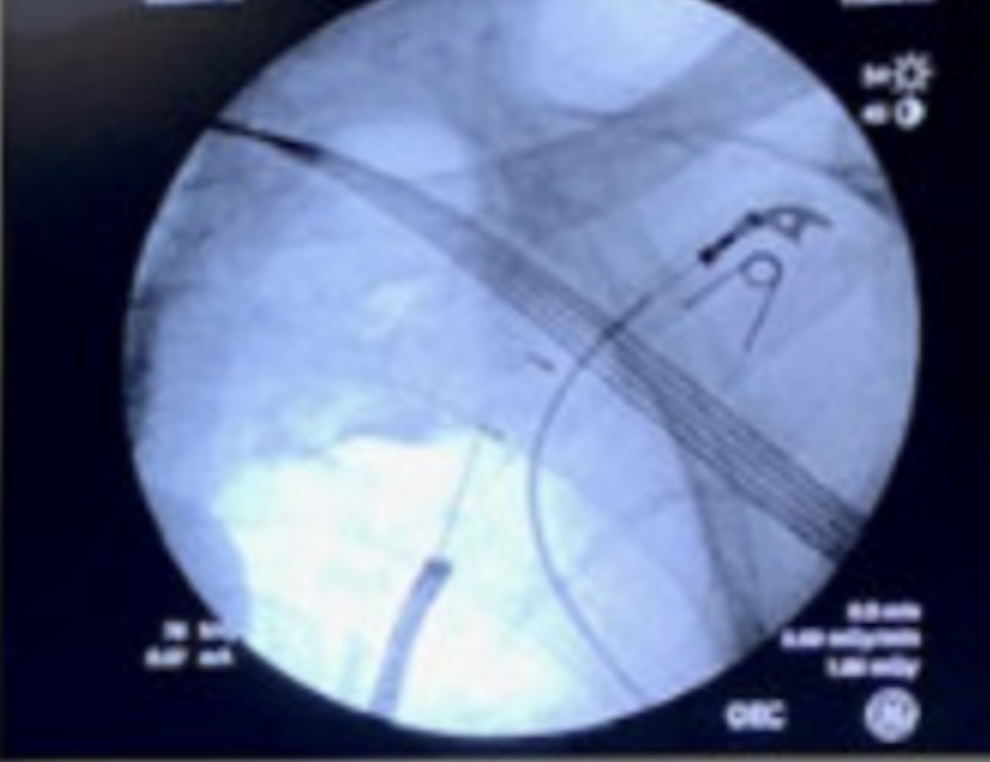

A multicenter prospective study of robotic-assisted bronchoscopy shows that RAB-guided sampling of peripheral pulmonary lesions compares favorably with results from sizable nonrobotic #bronchoscopy studies.

Read more in the August #JournalCHEST issue: hubs.la/Q03Cql920